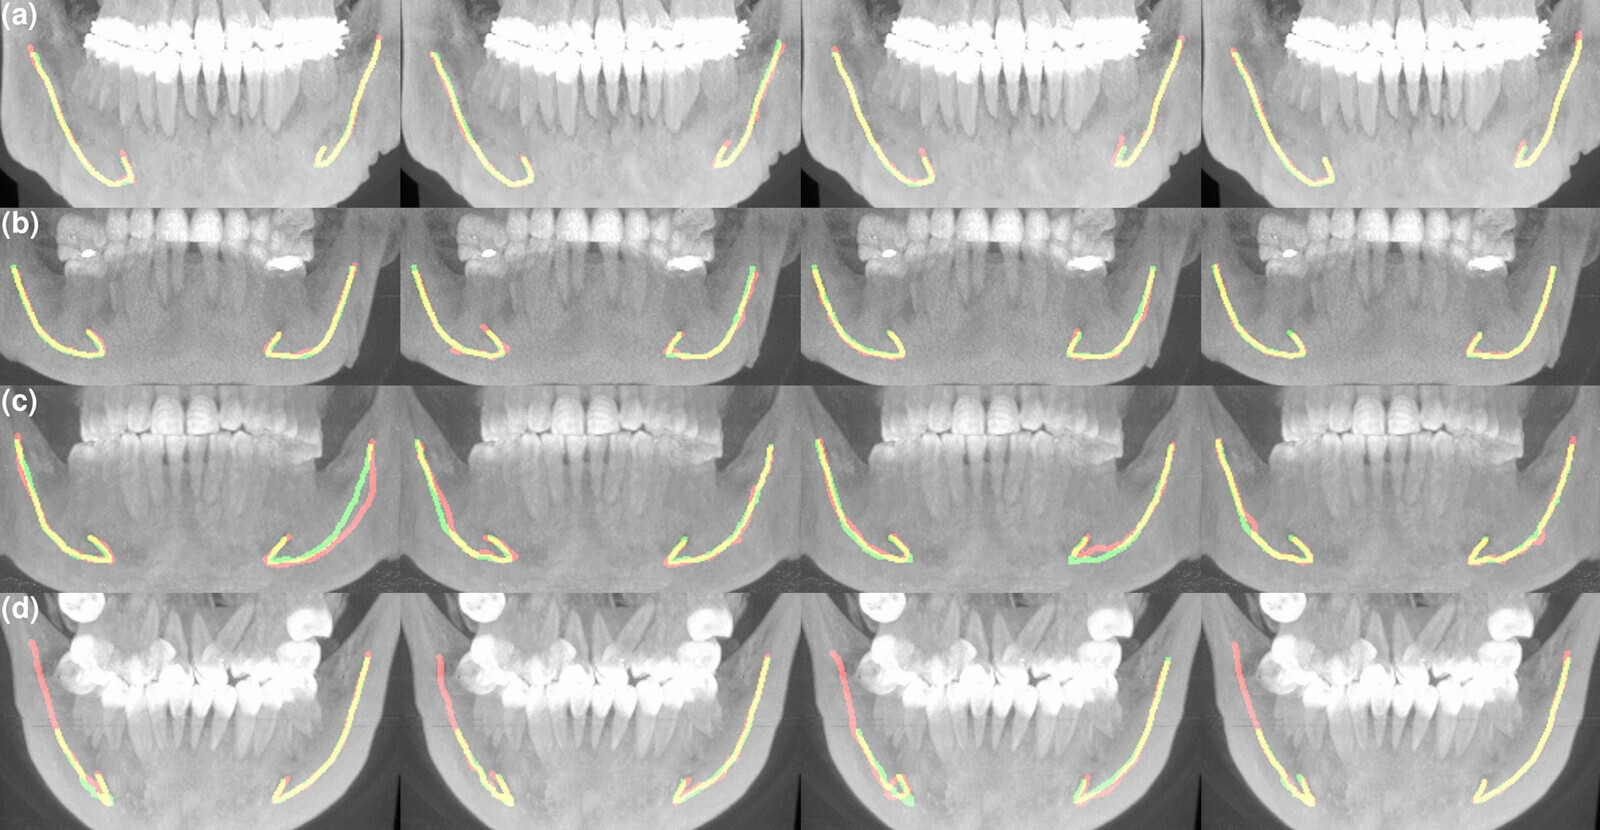

Researchers from Aalto University in Espoo, Planmeca and the Finnish Center for Artificial Intelligence (FCAI) developed a deep learning system and trained it with 3D images rendered with CBCT. The database consisted of images from five different CBCT scanners from four vendors and patient cohorts of two ethnicities—869 Finnish patients (79%) and 234 Thai patients (21%).

The performance of the deep learning system was clinically evaluated by comparing its results with those of four experienced dental and maxillofacial radiologists. The model accurately segmented the mandibular canal and performed better overall than the radiologists. In addition, it showed promising generalisability with regard to new CBCT scanners and ethnic groups.

“When a huge amount of data is fed to the neural network and the location of the mandibular canal is marked in it, it learns to optimise its own internal parameters. The neural network resulting from this learning quickly finds the mandibular canal from the individual 3D data input,” said co-author Vesa Varjonen, vice president of research and technology at dental equipment manufacturer Planmeca, which is based in Helsinki, in a press release.

“In clinical assessments, experts went through the results produced by the model and discovered that in 96% of the cases they were fully usable in clinical terms. We are highly confident that the model works well,” commented co-author Jaakko Sahlsten, a doctoral researcher at Aalto University.

“Tampere University Hospital provided us with extensive and versatile clinical materials produced with several 3D-imaging devices. The data was divided at random and part of it used for training the neural networks and part of it isolated for testing and validating the designed method,” said Sahlsten.